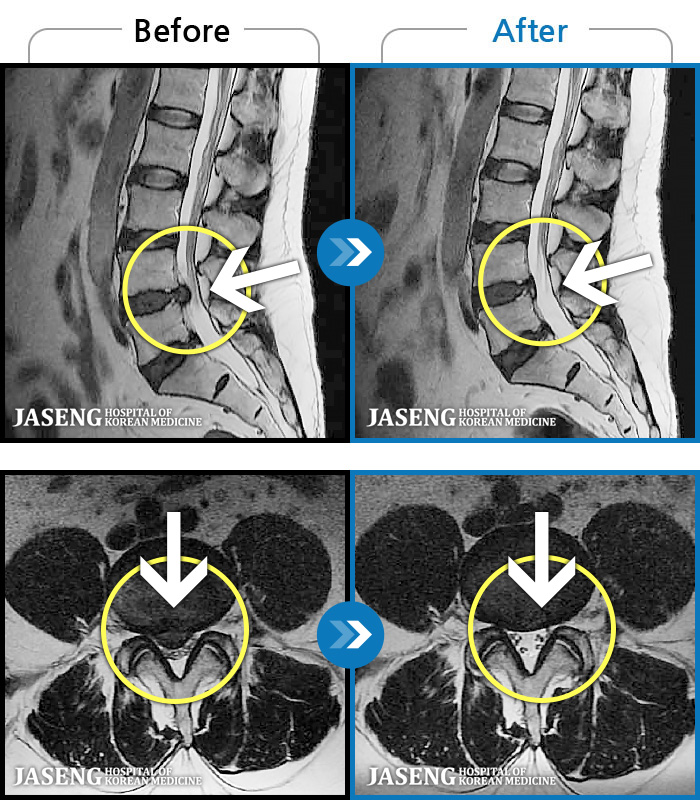

[뱸] 19.11.28~25.05.06